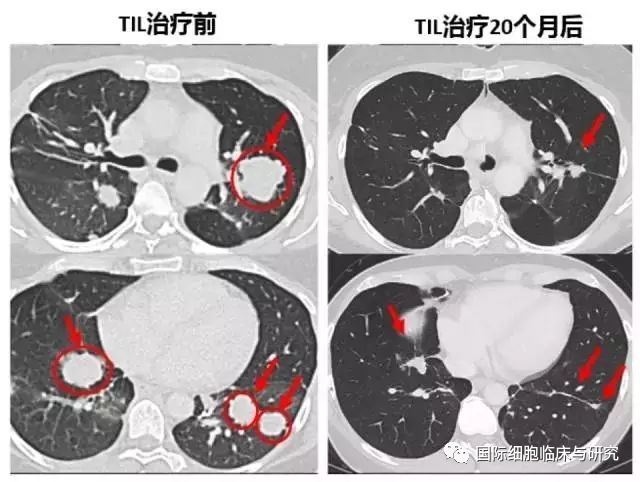

一名晚期胆管癌患者,出现肝转移和术后双肺多发转移。接受了靶向蛋白ERBB2IP突变的TIL疗法,效果十分明显。细胞回输后,全身肿瘤开始迅速缩小,体力恢复很快。第二次TIL治疗20个月后复查,这些肿瘤都非常显著的缩小了。

目前,该患者已经幸运的生存超过10年。